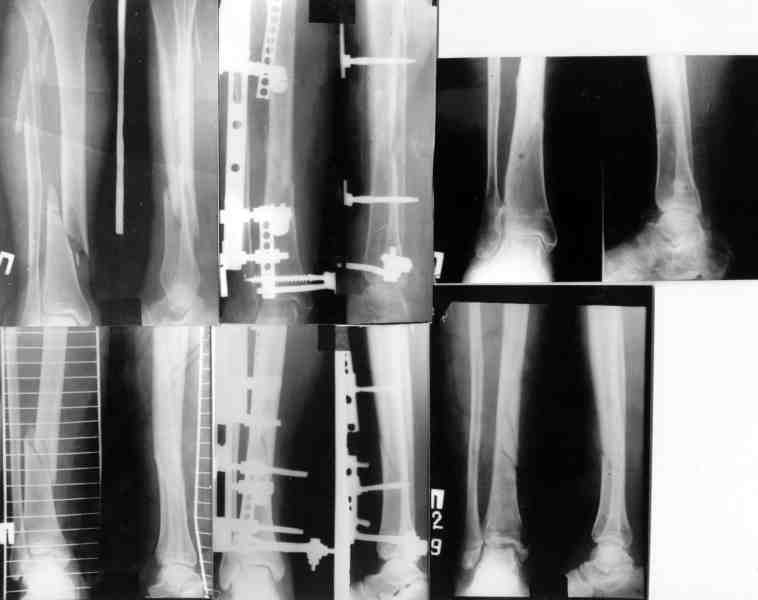

Вот еще информация, ознакамливайтесь pls/

С ув. Сергей Мелашенко,

Приморск, Запорожская обл.

Ukraine